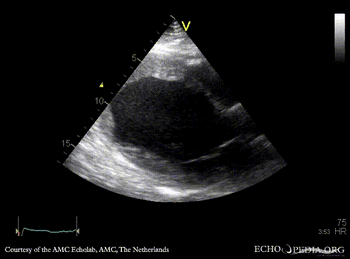

E00219.gif E00220.gif

PLAX: cardiac aneurysm, spontaneous echo contrast A4CH: cardiac aneurysm, spontaneous echo contrast